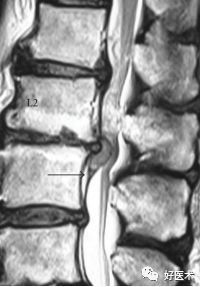

我们先来看一个病例:

诊断